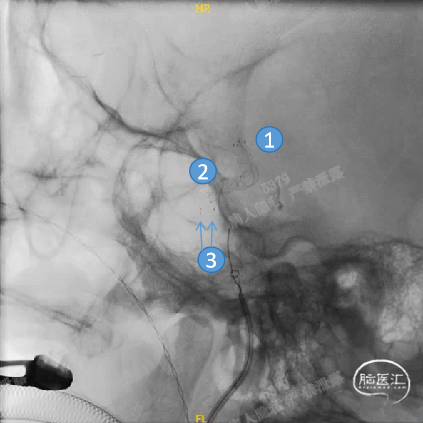

Headway™ 27 156cm微导管内输送FRED 4518血流导向密网支架,系统远端精准定位于预计着陆区以远3-5mm,回撤微导管原位释放支架,头端锚定在颈内末端处。

正位

①输送导丝头端

②支架远端扩口显影点

③有效段起始点

④支架近端扩口显影点

确认支架远端定位于计划位置,预估近端可完全覆盖动脉瘤颈,且锚定距离充足。继续平衡释放系统,确保支架整体充分打开且贴壁良好后,解脱支架。

工作角度

①支架远端扩口显影点

②有效段螺旋显影丝

③支架近端扩口显影点